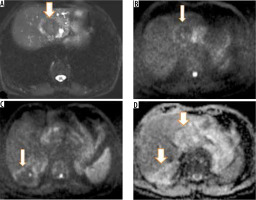

On non-contrast CT, 15 patients (65%) revealed hypodense hepatic mass with scattered foci of calcification with no associated cystic component (Figures 1 and 2). Four (17.3%) patients revealed complex hepatic mass with hypoattenuating cystic areas and hyperattenuating calcifications (Figure 3). Four (17.3%) patients revealed thick walled hypodense cystic lesion (Figure 4). None of the lesions showed intralesional enhancement in arterial, portal, or hepatic venous phase CT (Figures 1 and 2). Five cases showed mild peripheral irregular enhancement in hepatic venous phase. Hepatic atrophy with capsular retraction was seen in three cases. One patient had superadded infection with hepatic abscess formation that required pigtail catheter drainage. With regards to the extent of disease, seven patients showed peripheral hepatic lesions with no biliary or vascular involvement (P1). Biliary radical obstruction was seen in seven patients. Peripheral biliary radicals above the primary confluence were infiltrated in four (P2). Hepatic hilar involvement with both lobe biliary radical dilatation was seen in three patients (P3). Single hepatic vein involvement was seen in three patients (P2). Three patients showed combined infiltration of at least two hepatic veins (P3). Main portal vein encasement was seen in two patients, and two showed combined infiltration of both IVC and hepatic veins (P4) (Figure 5). Extra hepatic infiltration was seen in four cases including adrenal gland infiltration in two patients, parietal wall infiltration in one patient, and diaphragmatic invasion in one patient (Figure 6) (N1 disease). Three patients showed metastatic disease. Two among them had pulmonary involvement (Figure 6) and one had splenic involvement (M1 disease). A break up of the patients according to PNM staging is given in Table 2. On MRI all the patients showed hypointense signal intensity on T1-weighted sequence. On T2-weighted sequence one (5.2%) patient showed micro-vesicular cysts with no solid component (Kodama type 1) (Figure 3C). Six (31.5%) patients showed heterogeneous signal intensity mass with both hypointense solid and hyperintense cystic components (Kodama type 2) (Figure 3D). Two (10.5%) patients showed central hyperintense cystic component with surrounding hypointense solid component (Kodama type 3). Eight (42.1%) patients showed hypointense mass with no cystic component (Kodama type 4) (Figure 7). Two patients (10.5%) showed thick walled cystic lesions (Kodama type 5) (Table 3). Post-contrast T1-weighted images revealed no enhancement of the lesion. Three cases showed peripheral rim of enhancement in delayed phase. DWI revealed free diffusion characterised by low signal intensity on high b value DWI images and high signal on ADC in all cases (Figure 8) except one patient who had developed superadded infection with abscess formation and required pigtail drainage. Mean ADC value of HAE was 1.74 ± 0.48 × 10-3 mm2/s (range: 1.39 × 10-3 mm2/s to 2.3 × 10-3 mm2/s). Mean ADC of different Kodama types of HAE did not differ significantly from each other (p = 0.058) (Table 3). The mean ADC of the surrounding liver parenchyma was 1.10 ± 0.21 × 10-3 mm2/s.

Figure 8

A) Axial T2-weighted magnetic resonance (MR) image shows hypointense hepatic mass lesion in segment IVa. Corresponding diffusion image (b-value 800 s/mm) shows free diffusion in the lesion (hypointense signal). High b-value (800 s/mm) diffusion-weighted image of the same patient shows another non-restricting lesion in segment VI. D) Apparent diffusion values (ADC) image shows both the hepatic lesions (arrows) with high signal intensity (free diffusion) and ADC value of 1.65 × 10-3 mm2 per second

The internal structure of HAE determines the MRI appearance. On magnetic resonance imaging HAE exhibit heterogeneous signal intensity on T2W sequence with both hypointense and hyperintense areas. Hyperintense areas correspond to the cystic portions, whereas fibrous tissue-rich solid complements and intralesional calcification exhibit hypointense signal intensity. On T1W sequence the cysts also appear hypointense to surrounding normal hepatic parenchyma. Post-contrast study usually does not reveal any enhancement of the lesion, but a few lesions may show irregular peripheral enhancement owing to fibro inflammatory reactionary tissue at the peripheral of HAE [19-21]. MRI is also essential to reveal biliary or hepatic vascular involvement or extra hepatic extension of mass into surrounding organs. DWI performed using different b values of 0, 50, 400, and 800 s/mm2 is a useful adjunct to routine MRI. It usually shows non-restricted diffusion with low signal intensity on high b-value diffusion images (b value of 400 s/mm2 and above) and high signal on ADC images compared to surrounding hepatic parenchyma [22,23]. Restricted diffusion can be seen only in cases with superadded infection and abscess formation. The ADC value of HAE is more than that of malignant hepatic lesions and less than that of other cystic lesions of the liver. The presence of free diffusion with high mean ADC value in a solid infiltrative hepatic mass is a vital clue to its diagnosis as malignant hepatic tumours exhibit restricted diffusion Mean ADC of 1.31 ± 0.29 × 10-3 mm2/s for cholangiocarcinoma was previously reported by Cui et al., which is clearly lower than the ADC value of HAE [24].